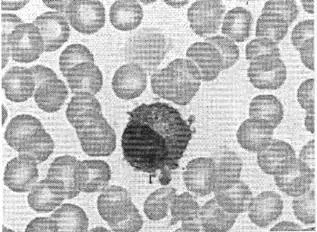

1.血涂片煌焦油蓝染色如图所示,标记序号1所指细胞为( )。

【答案】D

煌焦油蓝染色是网织红细胞特异性染色方法,网织红细胞内RNA的磷酸基带有负电荷,能与碱性染料煌焦油蓝带正电荷的有色反应基团结合,形成核酸与碱性染料复合物的多聚体,呈深染的颗粒状或网状结构。凡含两个以上的深染颗粒或具有线网状结构的无核红细胞,即为网织红细胞。